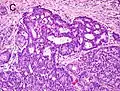

Gleason pattern 4. H&E stain.

• Pattern 4 - The tissue has few recognizable glands. Many cells are invading the surrounding tissue in neoplastic clumps. This corresponds to a poorly differentiated carcinoma.

Gleason 4

Gleason pattern 4 glands are no longer single/separated glands like those seen in patterns 1-3. They look fused together, difficult to distinguish, with rare lumen formation vs Gleason 1-3 which usually all have open lumens (spaces) within the glands, or can be cribriform-(resembling the cribriform plate/similar to a sieve: an item with many perforations). Fused glands are chains, nests, or groups of glands that are no longer entirely separated by stroma-(connective tissue that normally separates individual glands in this case). Fused glands contain occasional stroma giving the appearance of "partial" separation of the glands. Due to this partial separation, fused glands sometimes have a scalloped (think looking at a slice of bread with bite taken out of it) appearance at their edges.[4][7]